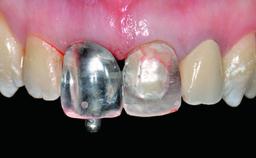

Replacement of a Compromised Upper Right Central Incisor: Hard- and Soft-tissue Augmentation, Late Placement of an RC Bone Level Implant

A 36-year-old male patient with a compromised maxillary central incisor was referred by his general dentist for consultation. The patient’s chief complaints were the gradual debonding of a temporary crown on the right central incisor and unsatisfactory esthetics due to an increasing diastema between the right central and lateral incisors. The patient reported a traumatic event some years previously, when a crown had been placed after root-canal treatment. The referring dentist wanted to provide a new crown restoration, but was concerned about the condition of the residual root. Anamnesis was negative for any other dental or periodontal pathology in the remaining dentition. The patient reported taking no medications: He was a smoker (10 to 15 cigs/day) and had realistic esthetic expectations.

Bone Augmentation Horizontal|Simultaneous|Staged

Augmentation Materials Xenogenous|Membrane

Soft Tissue Grafting Simultaneous

Prosthesis Type FDP